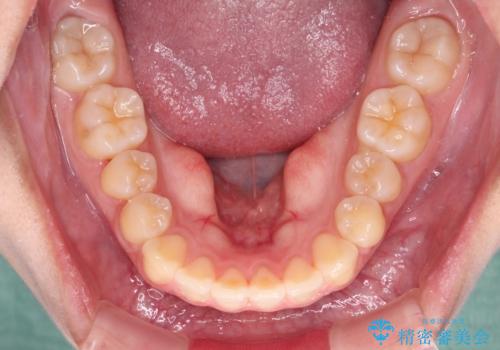

カリエールディスタライザーを併用したことで、確実かつ短期間で治療を終えることができました。